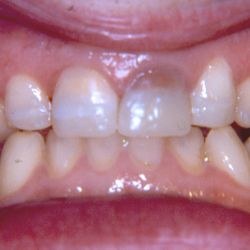

Ο 43χρονος αυτός ασθενής προσήλθε στο ιατρείο μας με έντονες αποτριβές των προσθίων και οπισθίων δοντιών του.

Ο αιτιολογικός παράγοντας για την καταστροφή της οδοντικής του ουσίας ήταν τα γαστρικά οξέα λόγω της χρόνιας γαστρο-οισοφαγικής παλινδρόμησης που παρουσίαζε.

Τα πρόσθια δόντια του αποκαταστάθηκαν με χτίσιμο σύνθετης ρητίνης επί τόπου ενώ τα οπίσθια δόντια του αποκαταστάσθηκαν με εργαστηριακά κατασκευασμένα επένθετα σύνθετης ρητίνης